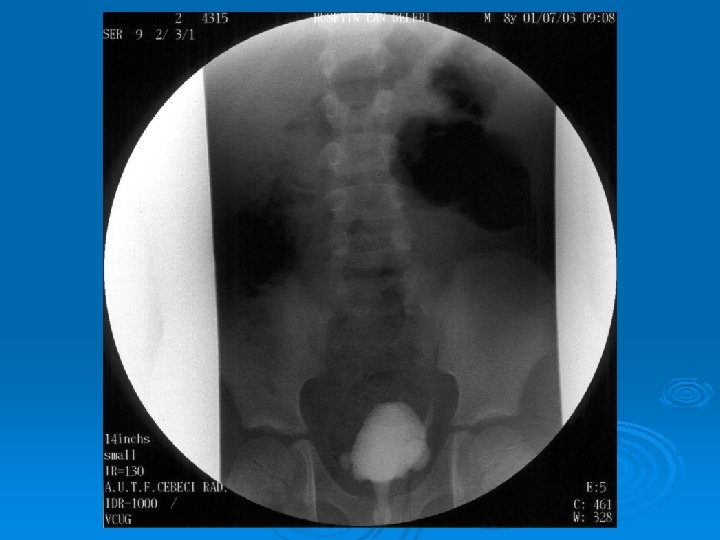

Çocukluk Çağında İdrar Yolu Enfeksiyonları İZLEMDE TANISAL GÖRÜNTÜLEME YÖNTEMLERİ Ø Miksiyon sistoüretrografisi: Vezikoüreteral geri kaçış (VÜR) görüntülenir. Ø DMSA sintigrafisi: Skar görüntülenir. Ø IVP: Tıkanıklık görüntülenir. Ø DTPA sintigrafisi: Tıkanıklık, böbrek fonksiyonları bozuk hastalarda atılım fonksiyonlarını değerlendirilebilir.